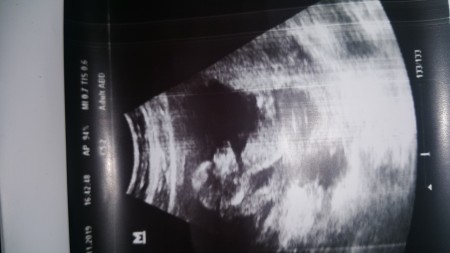

13+1 haftalik  görüntüsü

image